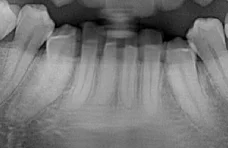

However, because this patient was scanned on a panoramic x-ray than can shift the focal trough, these apices can also be revealed. Again, this is done simply by using the data captured during the original scan – no additional scans are needed. You’ll notice that in this “layer”, the crowns are less visible. This is because the maxillary anteriors have dramatic angles to the emergence profiles and therefore the crowns are in a very different layer than the apices.